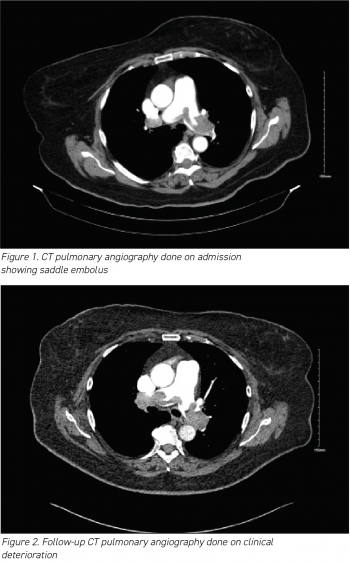

Here, we present a case of SPE in a tertiary care setting, providing insights into its clinical presentation and management. The patient, a woman in her 70s, presented with abrupt-onset dyspnoea, chest tightness and dizziness. Elevated D-dimers prompted a CT pulmonary angiography, revealing a saddle thrombus with bilateral emboli. Although initial anticoagulation therapy showed limited improvement, thrombolysis resulted in significant recovery. The patient was subsequently transitioned to a direct oral anticoagulant (DOAC) and discharged with plans for ongoing monitoring. This case highlights the complexities involved in successful management strategies for SPE, offering valuable insights for clinicians.

Saddle pulmonary embolism (PE) is a radiological term denoting a large clot that spans the bifurcation of the pulmonary artery trunk, often extending into bilateral main pulmonary arteries.6 It occurs in 2.6% to 5.4% of patients with PE.7,8 The presence of a large central thrombus in saddle PE may cause concern among clinicians, leading them to categorise it as massive PE and admit patients to the intensive care unit (ICU).

The results of her routine initial blood investigations are depicted in Table 1. Her initial blood workup revealed elevated D-dimers at > 4.00µg/ml (normal range 0.01 to 1.00µg/ml).